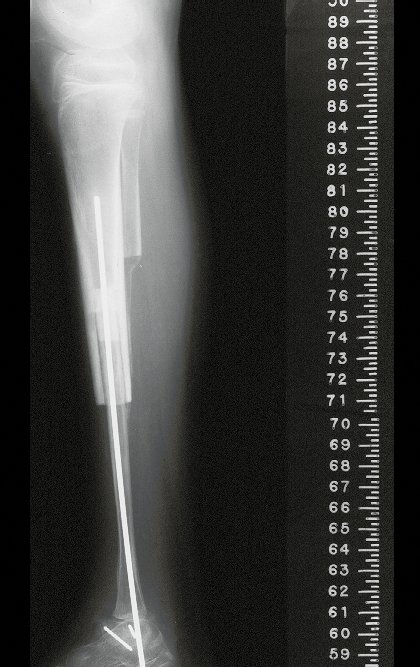

La cirugía se realiza con una incisión arqueada convexa medial comenzando al nivel de la cabeza del peroné, pasando por la superficie anterior de la pierna, hasta el final del maléolo lateral. La lesión se reseca con un margen oncológico macroscópico en los tejidos blandos y un margen óseo de 3,0 cm (fig. 5). Tras la resección del tumor, utilizando como guía la membrana interósea, se abordó el lugar de la osteotomía del peroné proximal, por encima de la emergencia de la arteria nutricia, confirmado mediante estudio arteriográfico previo (fig. 6). En este caso, como la resección del segmento tibial fue menor, abrimos una hendidura en la superficie lateral del segmento proximal de la tibia, de aproximadamente 3,5 cm de largo y lo suficientemente ancha como para permitir su enclavamiento, con una mínima desperiostización del extremo proximal. del segmento transpuesto, y sin perjudicar la nutrición proporcionada por la arteria nutricia. A continuación, retiramos el cartílago de la epífisis del peroné y tallamos un agujero en la cúpula (fig. 7) del astrágalo, permitiendo que encaje esta epífisis distal del peroné. Se continuó con el paso cuidadoso de un alambre de 2,5 mm de diámetro a través del canal medular del peroné, atravesando la placa fisaria. Este hilo continúa por la epífisis y pasa por el astrágalo y el calcáneo hasta aparecer en la piel (fig. 8).

En el postoperatorio inmediato se mantuvo la extremidad en inmovilización con el dispositivo crurópodo previamente elaborado. Seis semanas después de la cirugía se realizó una gammagrafía ósea con cortes axiales, comprobándose una buena vascularización del injerto (fig. 11). En la región metafisaria del peroné trasplantado, el aumento de la hipercaptación puede deberse a la vascularización de la propia placa fisaria y también al proceso reparativo en el sitio de la artrodesis talofibular. Los controles radiológicos de septiembre/98, nueve meses después de la cirugía, muestran la integración completa del peroné transpuesto, tanto proximal como distalmente. El engrosamiento del peroné ya es evidente y se puede distinguir fácilmente su placa de crecimiento (fig. 12).

La reconstrucción se realizó artrodesando la epífisis distal del peroné ipsilateral con el astrágalo, preservando la placa epifisaria del peroné. La evaluación postoperatoria preliminar mediante gammagrafía de corte axial demostró signos de captura del peroné en toda la extensión transpuesta y al nivel de la proyección de la placa de crecimiento del peroné distal. Aún no es posible distinguir la hipercaptura de la placa fisaria del proceso reparador de artrodesis a nivel del astrágalo. Los controles radiológicos de septiembre/98, nueve meses después de la cirugía, muestran la integración completa del peroné transpuesto, tanto proximal como distalmente. El engrosamiento del peroné ya es evidente y la placa de crecimiento del peroné se puede distinguir fácilmente.

La solución biológica en el tratamiento del osteosarcoma es una realidad cada vez más común en nuestro país y siempre debe ser considerada. Creemos que la presencia de hipercaptación ósea a nivel de la proyección de la placa fisaria del peroné distal en los exámenes de mapeo óseo puede ser evidencia de que es viable, aunque es imposible distinguir qué parte de este proceso se debe a reacción ósea. al nivel de fijación de la epífisis del peroné en el cuerpo del astrágalo. Considerando el corto período de seguimiento y el hecho de que se trata de un caso único, no es posible evaluar definitivamente el método de tratamiento utilizado. Lo que podemos decir con satisfacción, por el momento, es que los controles radiológicos de septiembre/98, nueve meses después de la cirugía, muestran una integración completa del peroné transpuesto, tanto proximal como distalmente. El engrosamiento del peroné ya es evidente y la placa de crecimiento del peroné se puede distinguir fácilmente. Creemos que se producirá un crecimiento y esperamos que haya una adaptación de esta placa fisaria, para que crezca con la velocidad de la tibia, ya que sabemos que la velocidad de crecimiento también está influenciada por la ubicación en la que se encuentra.